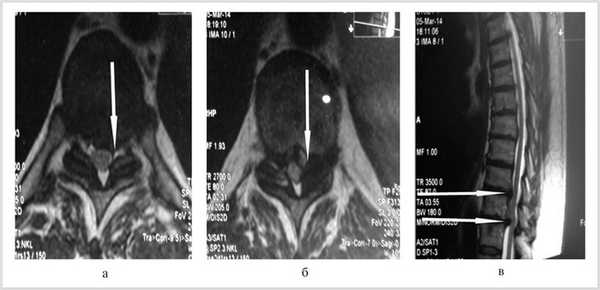

Больной обследован. При спондилографии грудного отдела позвоночника выявлен остеохондроз Th III —Th IV , II период, Th VIII —Th XII III период; данные MPT грудного отдела позвоночника: грыжи межпозвонковых дисков Th III —Th IV , Th IX —Th X , Th X —Th XI (рис. 1). При электронейромиографии нижних конечностей обнаружены выраженные изменения по аксональному типу в левом и правом малоберцовом нервах.

Рис. 1. Магнитно-резонансные томограммы грудного отдела позвоночника (Т1 режим): в аксиальной (а, б) и сагиттальной (в) плоскостях до операции.